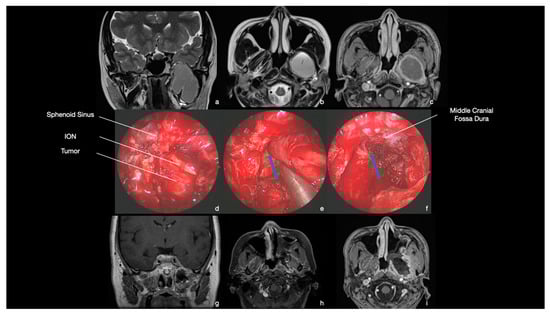

9.1. Case 1